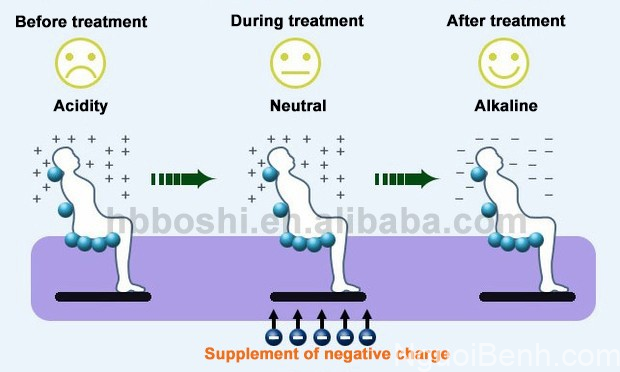

Điện trường là một môi trường có chứa điện tích. Vậy nên các điện tích có trong điện trường cao áp vừa được tạo ra sẽ tương tác với điện tích màng tế bào trong cơ thể người, từ đó kích thích tế bào trao đổi chất, điều chỉnh cân bằng axit-bazơ & chất điện giải trong máu, cải thiện chức năng thần kinh tự chủ, tăng cường khả năng miễn dịch… nhằm phòng ngừa và điều trị các loại bệnh lý. [15]

Quá trình cân bằng axit-bazơ, giúp cơ thể trở lại tính kiềm tự nhiên và khỏe mạnh khi trị liệu cùng máy điện trường cao áp